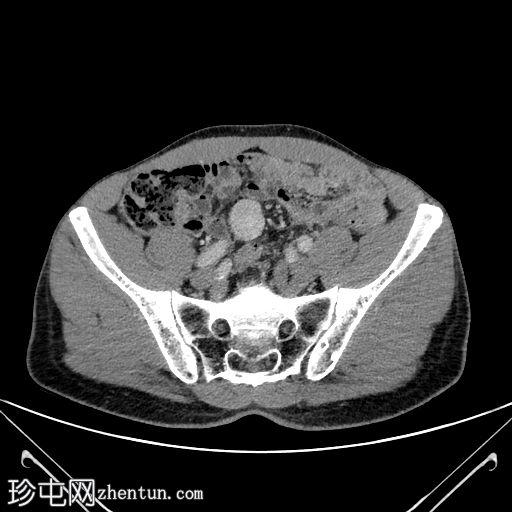

3.jpg

轴向C+期

门静脉期

边界清晰,单发,均匀强化,实性,无坏死,盆腔内肠系膜肿块病变。

无可疑区域淋巴结肿大,无相关钙化,亦无其他强化间叶病变。

周围结构未见明确侵犯。

下腔静脉扩张至3.6 cm,意义不明。